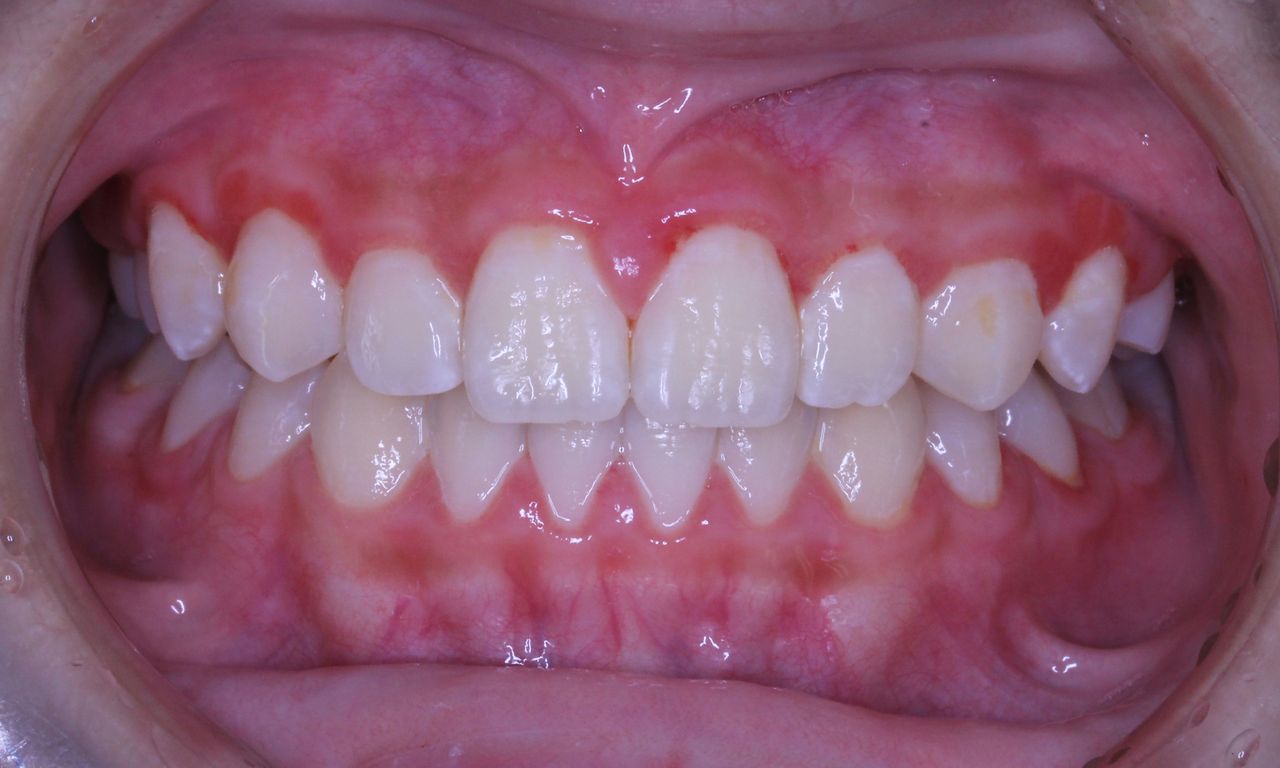

現在の状況です

中学2年生になりました。

上顎も下顎もそこそこの歯列になっていると思います。

咬み合わせも良好です

なんと、大人の歯は虫歯0本で管理されてます!

こういった部分は歯列矯正の技術的な部分はまったくなく、知識という部分をふんだんに応用した結果です。